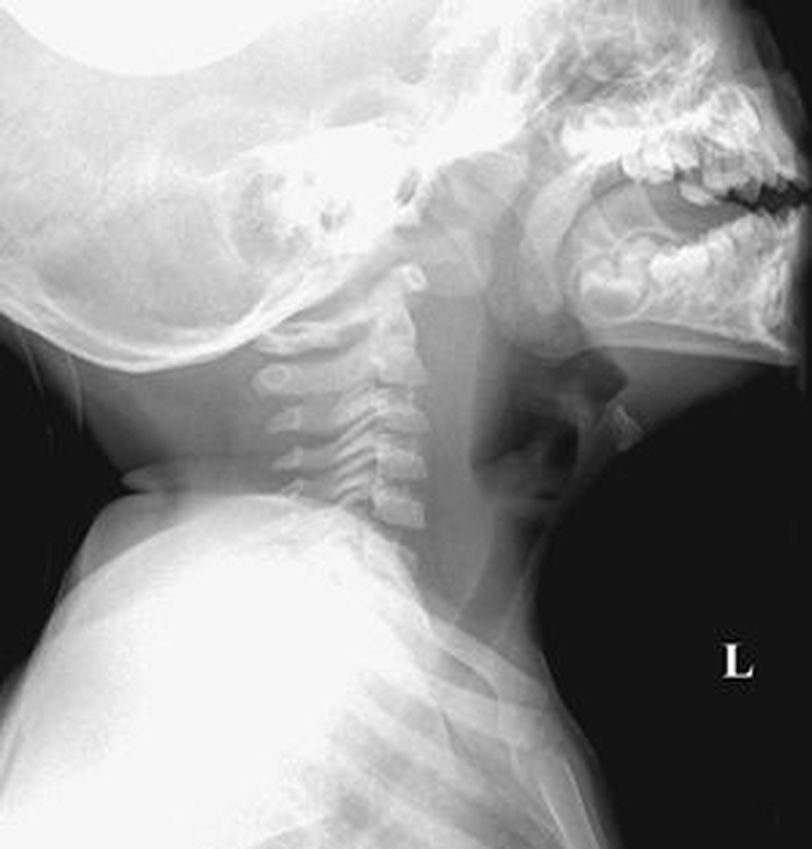

Retropharyngeal space is a potential space behind the pharynx. It extends from the base of the skull to a level of bifurcation of the trachea. This area has retropharyngeal nodes in children; these nodes disappear after 4 years of age. Retropharyngeal abscess is a potentially fatal infection of the neck. It occurs secondary to infection of the head and neck region that can spread through lymphatics. Trauma to the posterior wall of the pharynx can also cause a retropharyngeal abscess. The most common causative agent is streptococci. Retropharyngeal abscess is a disease of childhood. It occurs in children below 5 years. The patient presents with fever, pain in the neck, and torticollis. Dyspnea or stridor may also be present due to swelling obstructing the airway. X-ray lateral view of the neck is diagnostic. It shows the increased thickness of soft tissue in the prevertebral region. The normal curvature of the cervical vertebra is lost secondary to a spasm of muscles. Treatment involves incision and drainage. Systemic antibiotics are administered through the parenteral route. Source https://radiologykey.com/26-retropharyngeal-abscess/